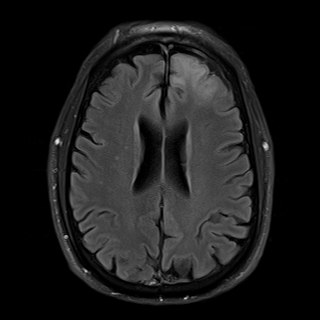

Managed AI engineers on embodied agents, MRI compressed sensing, AlphaZero open-source; contributed to fastMRI website/dataset release and competition kick-off

- Supported open-source AI research including fastMRI dataset release with NYU Langone

engineering-management

AI-research

medical-AI

open-source